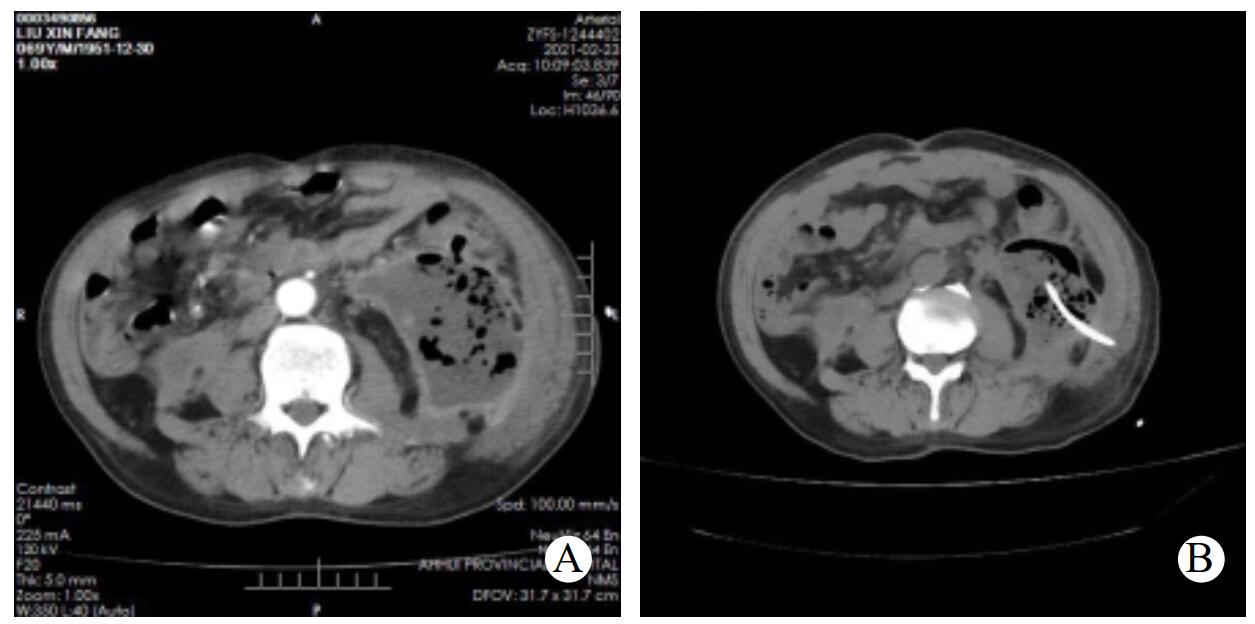

步骤一,经皮穿刺置管引流(pereutaneous catheter drainage, PCD):诊断明确的感染性胰腺坏死的患者,局部麻醉,在CT引导下选择合适的穿刺路径,尽量避开肝脾等实质脏器及胃肠道等消化道,采用Seldinger法穿刺置入14 F或16 F管径的猪尾巴引流导管,见图 1。置管成功后即可抽取脓腔内的液体留作细菌培养及药敏试验,后每日经引流导管给予生理盐水间断冲洗两次,一般以冲洗液无明显脓性液体或沉渣为标准。

A:CT增强CT提示左侧腹膜后感染性胰腺坏死;B:CT引导下PCD置入猪尾巴导管 图 1 行PCD治疗前及PCD后CT表现